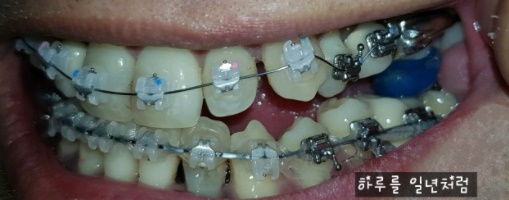

너무 많이 뒤죽박죽 되어 있었던 내 치아들을 얇은 와이어줄과, 굵은 와이어 줄을 교체하 가면서 치아들을 조금씩 자리잡아 갔었고,

위 사진과 비교해 보면 치아들이 상당히 가지런히 된 모습이다.